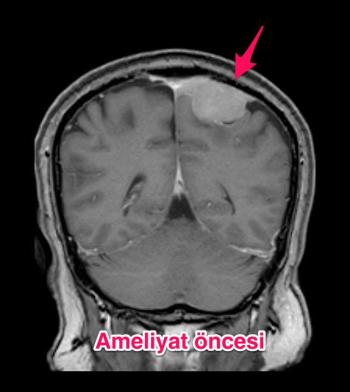

Genel

Genel Beyinde kanser nasıl oluşur? Beyinde kanser, herhangi bir diğer dokudaki kanser gibi oluşur. Organlar dokulardan, dokular da hücrelerden oluş...